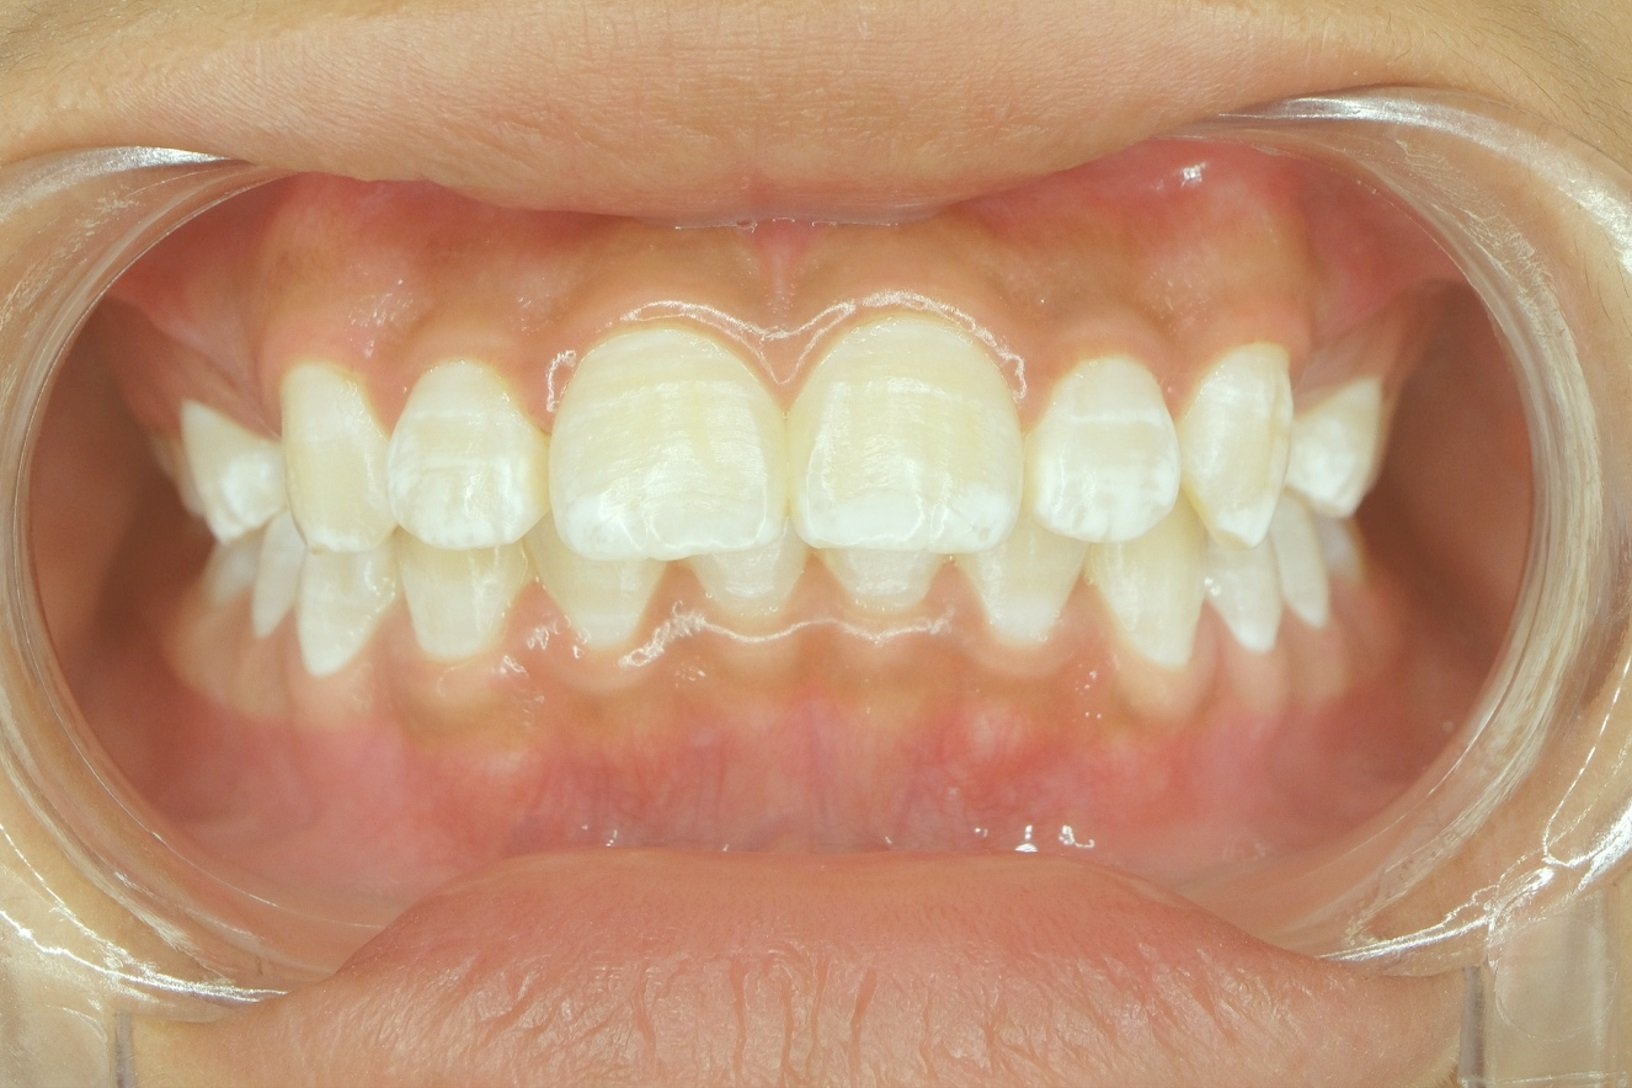

Preventative measures such as maintaining good oral hygiene, quitting smoking, and avoiding irritants that can cause canker sores can help reduce the risk of developing white dots on the gums. Regular dental check-ups and screenings can also help detect any oral health issues at an early stage.